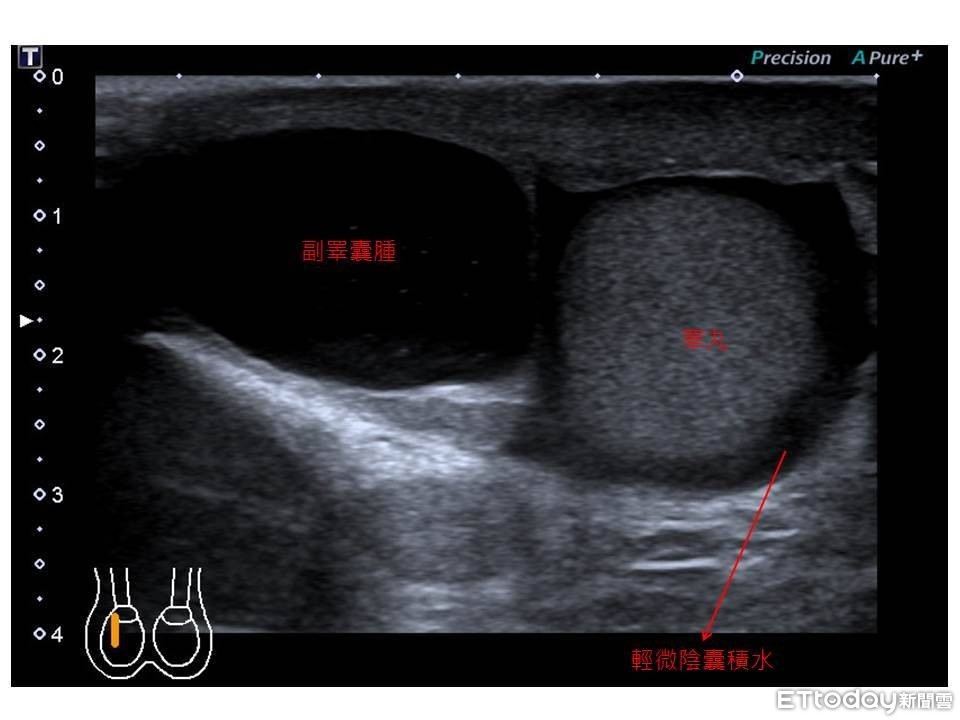

收治患者的書田診所泌尿科主任醫師周固表示,張先生到診間自述「走路也會痛」,經觸診及超音波檢查發現陰囊大小約7.5公分x7公分x3公分,診斷為副睪囊腫合併陰囊水腫,建議先暫停激烈運動,穿著寬鬆衣物,倘陰囊有摩擦破皮使用外用藥物防止感染,疫情和緩後以手術治療。

周固提到,造成陰囊腫大的可能原因有副睪囊腫、睪丸腫瘤、睪丸和副睪丸發炎、陰囊水腫。此次的案例是因副睪囊腫引起陰囊腫大,而副睪囊腫的發生原因,推測可能與感染或創傷有關,多發生於40歲以上男性,觸診時可摸到腫塊,超音波及透光檢查可見透明水囊。